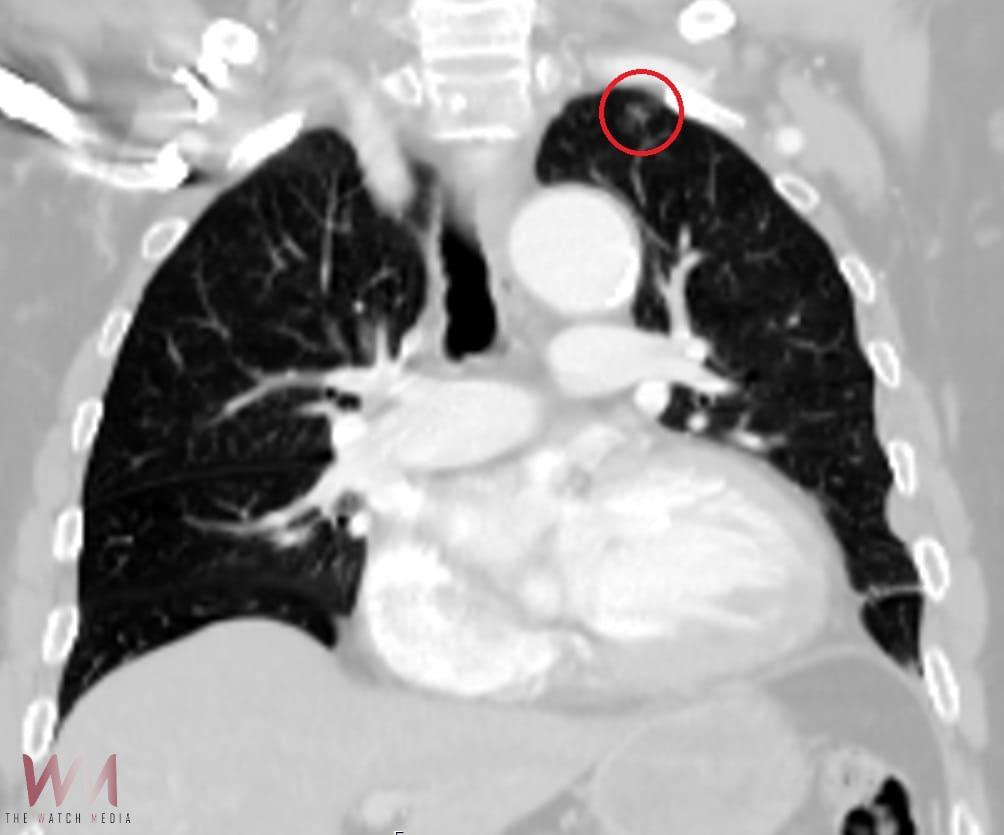

電腦斷層時,意外發現林姓男子肺部邊緣出現0.9公分的肺結節陰影《紅圈處》。(圖/光田綜合醫院提供)

(觀傳媒中彰投新聞)【記者廖妙茜/台中報導】在所有肺癌中,肺腺癌最常見且早期多無症狀。光田綜合醫院胸腔外科陳紀寰醫師表示,當天接獲急診通報,一名車禍林姓男子因嚴重胸部創傷,緊急送至本院急診。經 X 光與電腦斷層檢查,診斷多處肋骨錯位骨折,且伴隨明顯胸腔積血,建議進行手術以清除血塊與骨折復位固定。沒想到,就在醫師與影像醫學科團隊仔細檢視電腦斷層時,意外發現林先生肺部邊緣出現一處僅0.9公分的肺結節陰影,高度懷疑是早期肺腺癌。就這樣,讓這個原本可能潛伏多年、毫無症狀的病灶,因車禍而被提早發現。